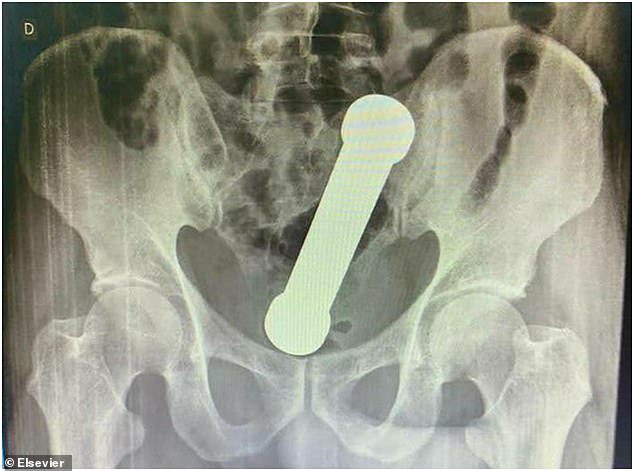

ชายอายุ 54 ในบราซิลเข้ารักษาตัวในโรงพยาบาลหลังมีอาการปวดท้องถ่ายไม่ออกเพราะมีดัมเบลหนัก 2 กก.ยาว 20 ซม.อยู่ในทวาร จริงๆ มันติดอยู่ในนั้นมาสองวันแล้วเจ้าตัวพยายามเอาออกเองแต่ไม่สำเร็จ หมอต้องใช้มือล้วงเข้าไปเกือบสุดแขนเพื่อดึงมันออกมา